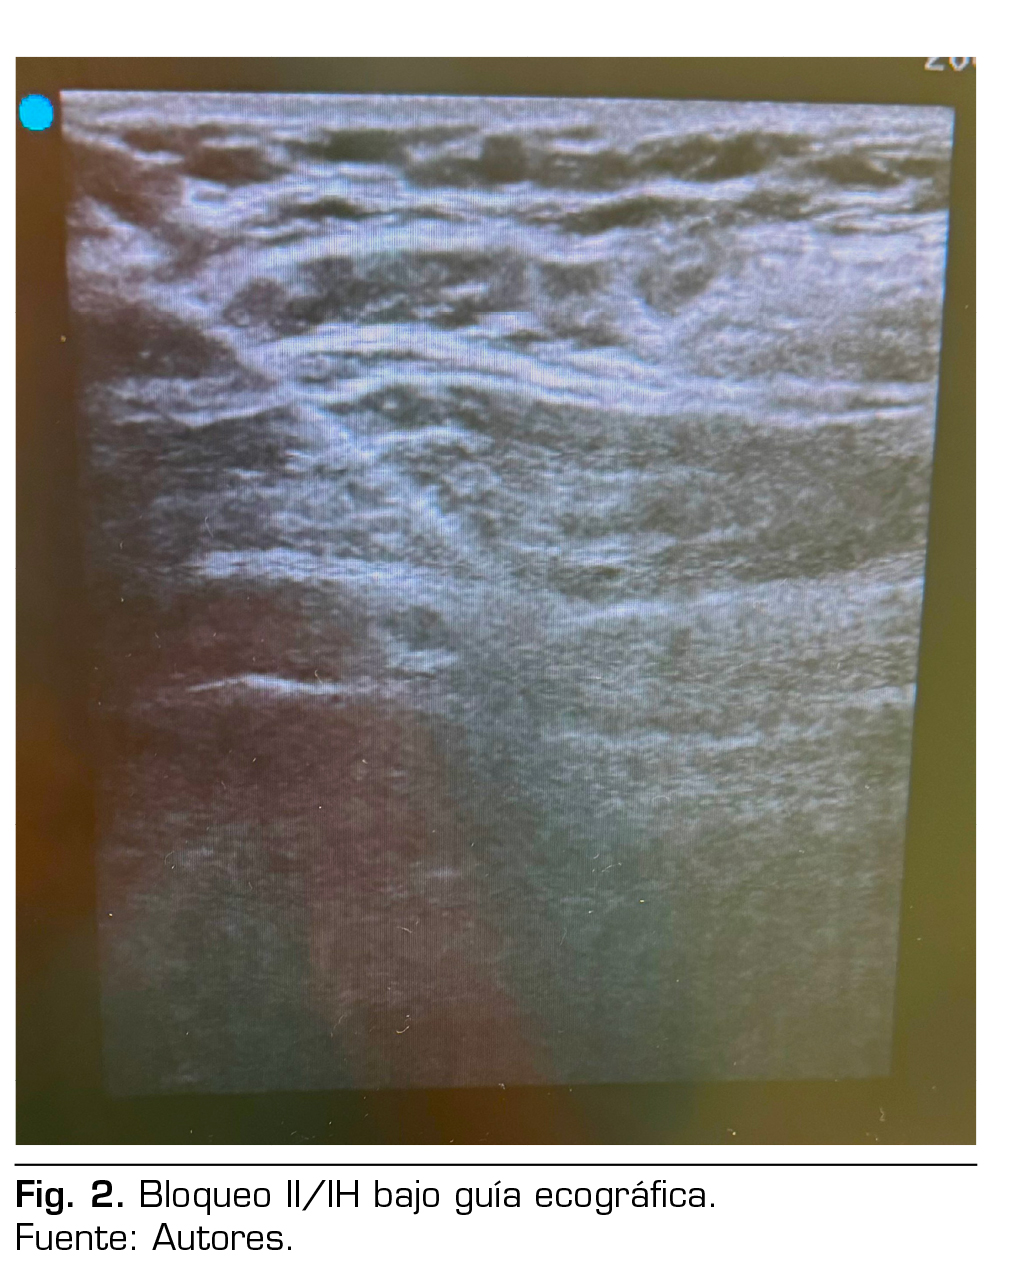

Por lo anterior, se define como técnica anestésica y analgésica bloqueo II/IH bajo guía ecográfica. Posicionamos a la paciente en decúbito supino, previa monitorización ASA básica, se realiza asepsia en zona de punción, se usó una sonda lineal estéril de alta frecuencia, se ubicó entre la cresta iliaca anterosupeior y la cicatriz umbilical, orientándolo un poco más cefálico de lo habitual; en esta posición se logra visualizar los nervios ilioinguinal e iliohipogástrico entre el músculo transverso del abdomen y el músculo oblicuo interno como se muestra en la Figura 2. Después de la visualización, se utilizó una aguja 22 G de 50 mm abordaje en plano; previa aspiración se inyectó ropivacaína a una concentración de 0,75 % con un volumen aproximado de 10 ml. Posteriormente procedimos a realizar sedación con propofol 2 mg/kg/h, se mantuvo en puntuación de 3 en la escala de Ramsay, sin cambios hemodinámicos de importancia, además se administró dexametasona a dosis de 4 mg en el intraoperatorio y coadyuvantes analgésicos como paracetamol y metamizol. Tras la hernioplastia de abordaje abierto con tiempo quirúrgico de 35 min, sin complicaciones o incidencias, se la traslada al área de recuperación postoperatoria según protocolo, con evaluación de puntuación de dolor mediante escala visual analógica 2 de 10. Hemodinámicamente estable y con dolor controlado, cumple criterios de alta médica; se usó el sistema de puntuación postanestésico para determinar si la paciente está preparada para ir a casa, obteniendo un puntaje de 9 según el protocolo del hospital; se deja pautada analgesia de rescate para domicilio con paracetamol y antinflamatorios condicionados según dolor.